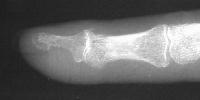

Clinical Example: Breast cancer metastatic to fingertip

Breast cancer is known to metastasize widely. This patient with poorly differentiated breast cancer developed a fingertip mass. Biopsy confirmed metastasis, but she declined further surgery.

Probable erosive changes of adjacent distal phalanx.